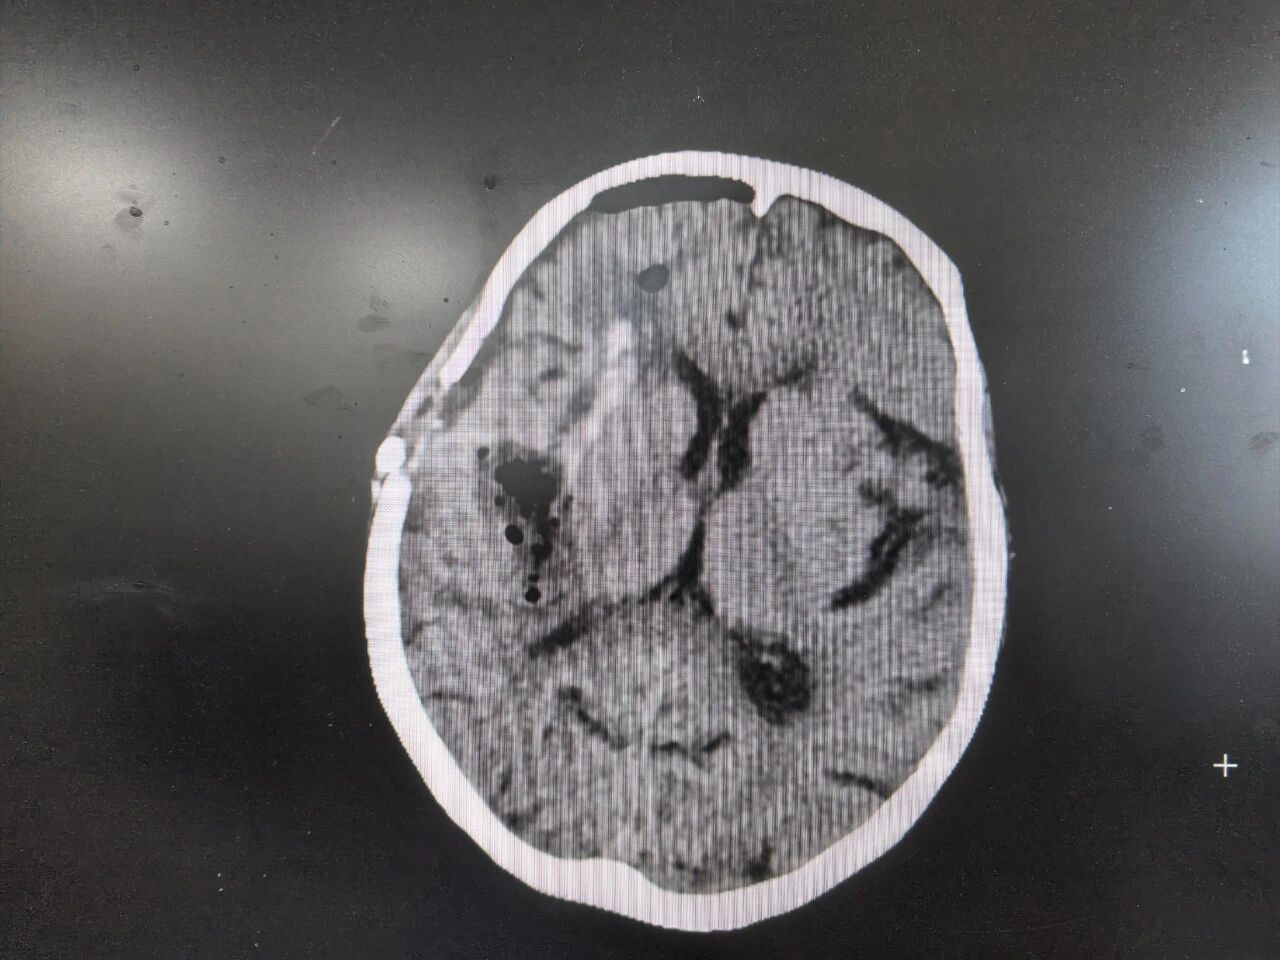

紧急CT扫描结果令人倒吸一口凉气:梁奶奶右侧基底节区(大脑深处要害区域)大量出血,脑疝形成,血块体积巨大,形如“铸型”压迫着脆弱的生命中枢,中线结构被挤压得严重偏移——这是典型的高血压脑出血,且已发展到致命阶段。每一分每一秒的拖延,都意味着脑细胞不可逆转的死亡和生存希望的渺茫。

术前CT:大量血肿压迫